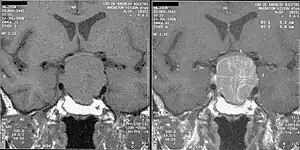

Adenoma de hipófise ou de pituitária é um tumor não-maligno que ocorre na hipófise. Os adenomas de hipófise são, geralmente, divididos em três categorias, dependendo de seu comportamento biológico: adenoma benigno, adenoma invasivo ou carcinoma. Na maioria dos casos trata-se de adenoma benigno e aproximadamente 35% correspondem a adenomas invasivos,[1] enquanto apenas de 0,1% a 0,2% são carcinomas.[2][3] O tumor de pituitária representa de 10% a 25% de todas as neoplasias intracranianas[4] e a prevalência média na população em geral é de quase 17%.[5]

Os adenomas que excedem o tamanho de 10 mm são definidos como macroadenomas e aqueles inferiores a 10 mm são referidos como microadenomas. A maioria dos adenomas de hipófise é classificada como microadenoma e tem uma prevalência estimada em 16,7% (14,4% nos estudos em autópsias e 22,5% em estudos radiológicos).[5][6] Grande parte dos microadenomas de hipófise frequentemente não é diagnosticada e aqueles que chegam a ser diagnosticados são caracterizados como um achado incidental.

A dura-máter, o crânio e o osso esfenoide podem ser invadidos pelos adenomas de hipófise em sua forma invasiva. Embora, anteriormente, tenha-se acreditado que os adenomas de pituitária clinicamente ativos fossem raros, estudos recentes têm sugerido que eles podem afetar aproximadamente uma pessoa em 1000, na população em geral.[7]